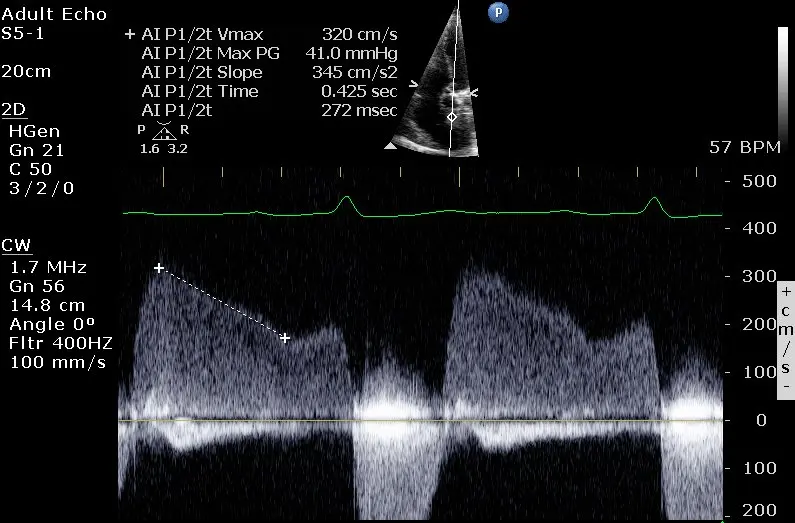

LV End-Diastolic Pressure (LVEDP)

📝 We use DBP as a proxy for aorta diastolic pressure.

In the above Doppler tracing, is 2 m/s. This example also illustrates the ‘a-dip’ that can sometimes be seen with Aortic Regurgitation.